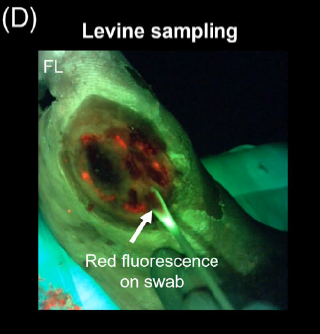

The “C-Swab” test: a technique for identifying bacteria in sinus tracts or tunneled wounds utilizing a cotton swab and bacterial fluorescence imaging

Andersen C. and McLeod K. Wounds 2025

Use of fluorescence imaging (FL) to optimize location of tissue sampling in hard-to-heal wounds

Serena, TE et al. Front Cell Infect Microbiol 2022